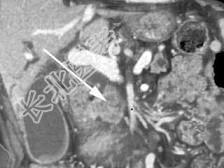

- 单项选择题关于该胰腺团块,结合图像, 最可能的诊断是 ( )

A、肠系膜上静脉受侵犯

B、门静脉栓塞

C、肠系膜上动脉受侵犯

D、以上都正确

E、以上都不正确